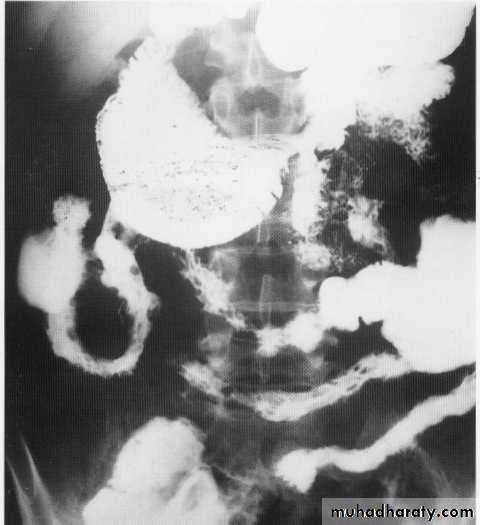

SB obstruct.

Small bowel contrast study

Barium follow throw x- rayCt scan with oral contrast